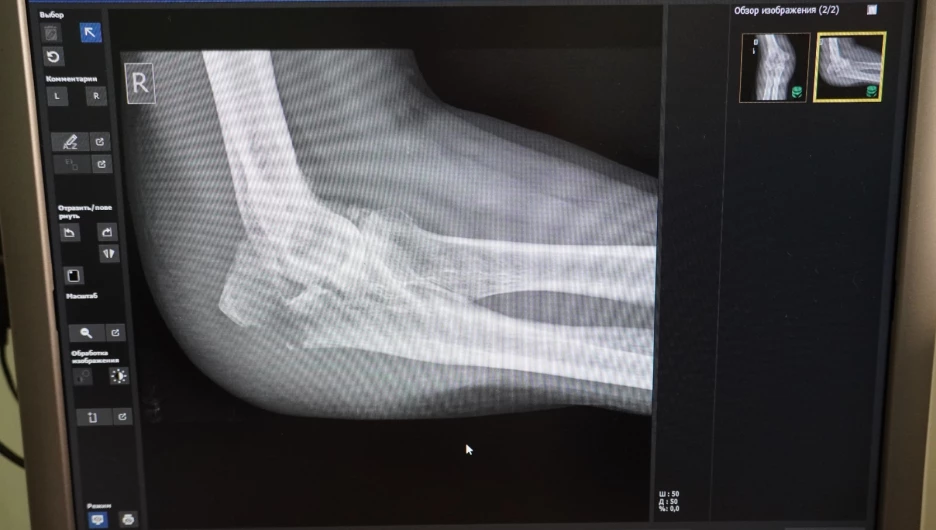

Самые уязвимые части тела в период гололедицы — это нижние и верхние конечности, говорит Константин Карапыш. Первыми под удар попадают нижняя треть предплечья и лодыжки — область голеностопного сустава.

Это связано с тем, что, поскользнувшись, человек рефлекторно выставляет руку вперед и падает на нее всем своим весом. Отсюда самая распространенная травма — перелом дистального метаэпифиза лучевой кости.

Лодыжку же человек повреждает, поскользнувшись на каком-нибудь бугристом месте. Нога подворачивается внутрь или наружу — связки испытывают сверхнатяжение, из-за чего кость буквально лопается.

За зиму врачи-травматологи сталкиваются с самыми разными травмами, полученными из-за гололедицы — чаще всего это ушибы, растяжения, вывихи крупных и мелких суставов, а также переломы. Врач подчеркнул, что не специалисту отличить одно от другого совсем непросто. Поврежденная конечность одинаково отекает, появляются гематома и болезненность. Из-за этого люди могут не обращаться к врачу несколько дней, надеясь, что все пройдет само.

«Так делать точно не стоит. Если вы получили травму, то стоит как можно скорее обратиться в травмпункт. Там сделают рентген-снимок, и после этого врач точно скажет, ушиб это или серьезный перелом, а после назначит лечение», — предупреждает травматолог.

От вида и степени травмы будет зависеть лечение и время восстановления. Так, поврежденная лодыжка без смещения будет заживать шесть недель. А при оскольчатом переломе человеку может потребоваться оперативное вмешательство и долгая реабилитация.